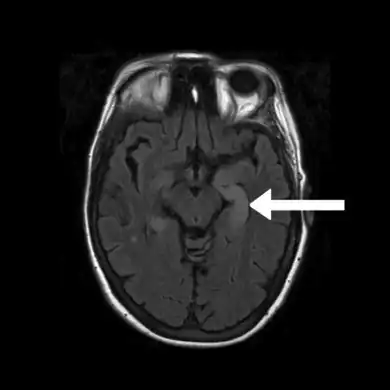

Neuroimaging

Brain MRI is the mainstay of initial investigation pointing to limbic lobe pathology revealing increased T2 signal involving one or both temporal lobes in most cases.[22][14]

Serial MRI in LE starts as an acute disease with uni- or bilateral swollen temporomesial structures that are hyperintense on fluid attenuation inversion recovery and T2-weighted sequences. Swelling and hyperintensity may persist over months to years, but in most cases progressive temporomesial atrophy develops.[23]